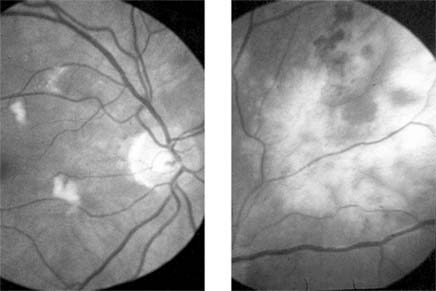

SUBACUTE INFECTIVE ENDOCARDITIS

Inflammatory changes on the cardiac valves may produce multiple embolization with frequent ocular manifestations that range from retinal and choroidal infarction to a mild infective vitritis. The emboli may arise from vegetations on the cardiac valves and may be composed of platelet and fibrinogen aggregates or calcified endocardial vegetations (Figure 15-13).

Figure 15-13

Figure 15-13: Subacute bacterial endocarditis. Calcific embolus impacted in arteriole below the disk, producing a distal area of retinal infarction.

HEMATOLOGIC & LYMPHATIC DISORDERS